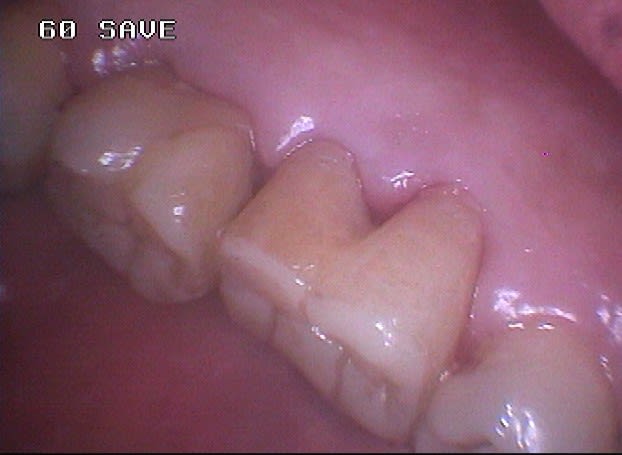

J'ai déjà récupéré de nombreuses racines à ce stade et les ai utilisées comme piliers de bridges ou les ai couronnées, dans la mesure ou l'ancrage alvéolaire était solide et en respectant les furcations pour y assurer l'hygiène.

La gencive lasérisée devient très ferme avec le temps et le déchaussement se stabilise. Ces restaurations se comportent bien sur un recul de plusieurs années.

Un exemple: une 46 avec furcation linguale dénudée après lasérisation et restauration par une endocouronne céromère réalisée il y a 9 ans et sans signe clinique avec une excellente attache gingivale malgré la perte osseuse, les 3 avant dernières images ont été prises lors d'un contrôle en mars dernier ...

9 années pour cette patiente de 90 ans, cela vaut bien le coup d'essayer vous ne croyez-pas? (dernière radio)

Avec le laser, on devient bien plus conservateur...